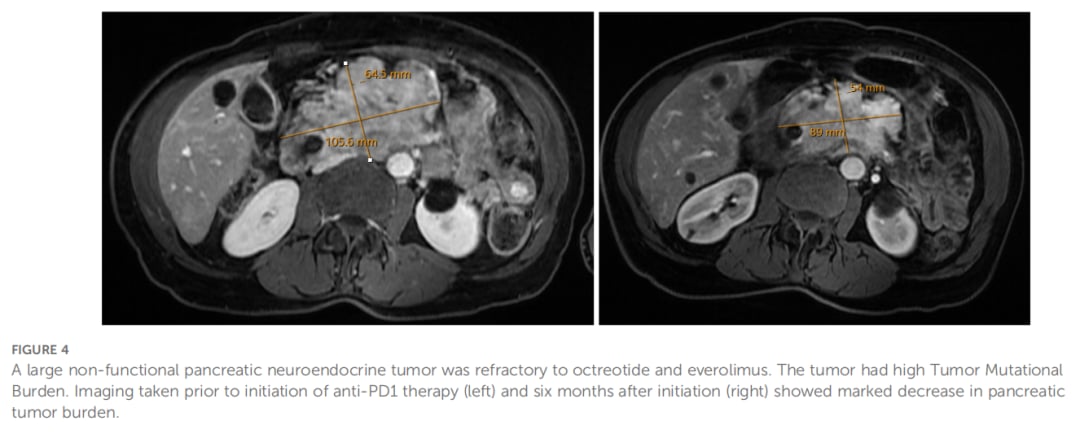

对患者肿瘤样本进行下一代测序,检测到TP53和TSC2基因突变,更重要的是,肿瘤突变负荷(TMB)高达10.5 muts/Mb,处于高水平(排位89%)。尽管此时PD-L1表达为阴性,但基于高TMB状态,在继续奥曲肽和依维莫司治疗的基础上,加用了帕博利珠单抗。

联合治疗带来了转机。启动帕博利珠单抗治疗6个月后,影像学检查显示胰腺原发肿瘤及门静脉周围淋巴结均较前缩小,9个月时肿瘤体积进一步减小。截至本文撰写时,患者接受帕博利珠单抗治疗已超过两年,疾病仍维持控制状态。此案例表明,对于PNET,即使PD-L1阴性,高TMB也可能预示着对免疫治疗的良好应答。

▲图4 胰腺神经内分泌肿瘤对奥曲肽和依维莫司具有耐药性